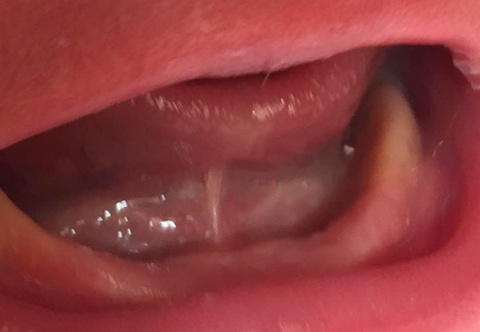

Type 3 Ankyloglossia